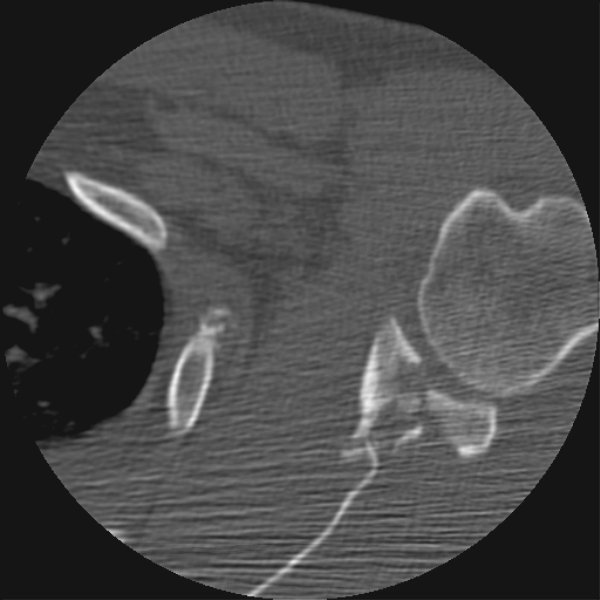

Return to Glenoid Fracture